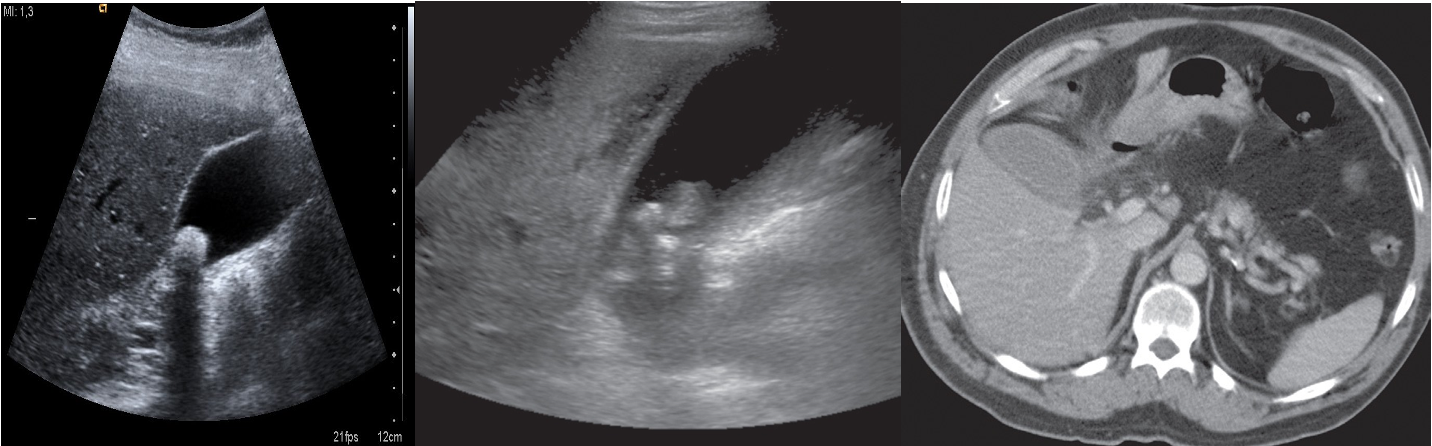

Imaging: Ultrasound abdomen will show distended gallbladder with thick wall, peri-cholecystic fluids and positive ultrasound prop Murphy’s sign.